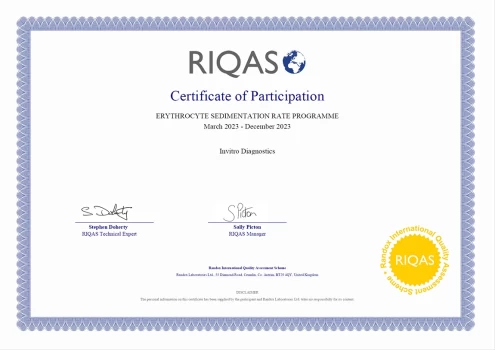

Certificate